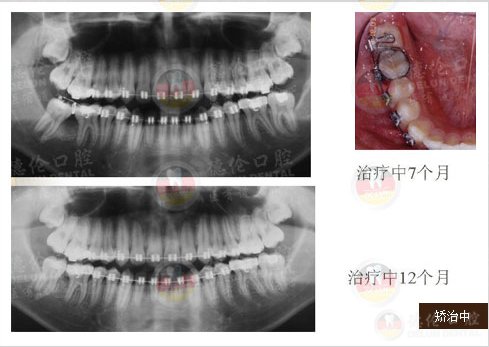

男 17岁

牙齿症状:下颌右侧第二、第三磨牙水平阻生,下颌左侧第三磨牙水平阻生

矫治方法:下颌拔除两颗第三磨牙(智慧齿)

发表于全球口腔正畸学界著名杂志J.Clin.Orthod